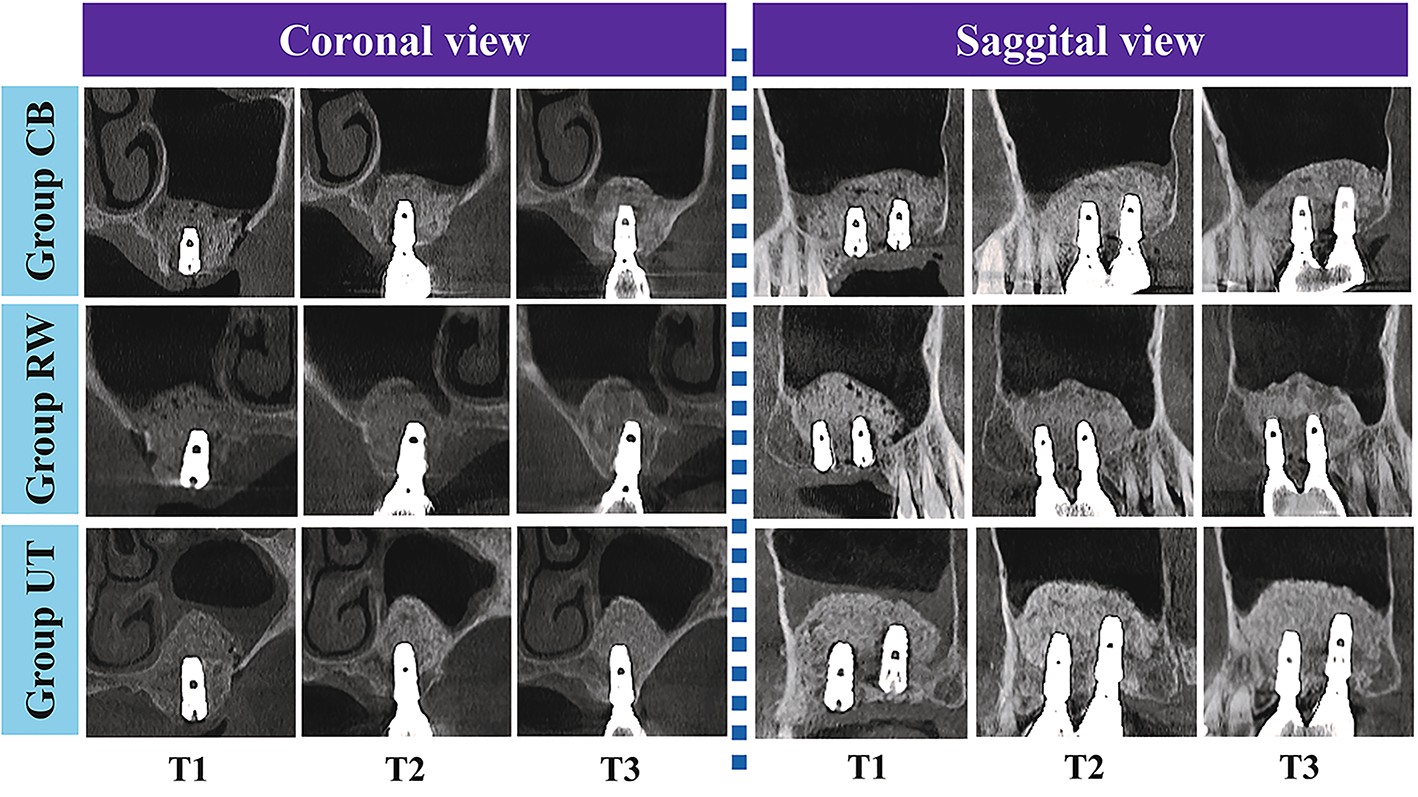

Representative radiographic images for the groups.